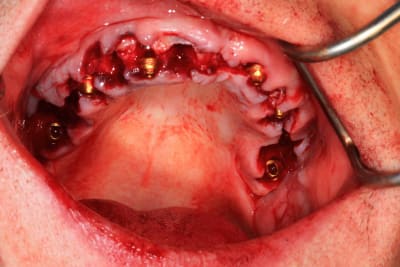

Le cas N°2 en images reelles :)

Guide métal avec support clavette, os assez fin : il est prévu un sticky bone complet : donc : lambeau avant extraction, positionnement du guide base et forage des clavettes, positionnement du guide implant, pose des piliers MU, controle des axes prothétique avec le guide pilier, collage des piliers prov sur le bridge a armature métal, occlusion nickel, sticky bone et PRF, sutures suspendues.

Il n’y a pas trop de déviation , surtout quand on regarde l’apex de l’implant 25 qui affleure voir pénétre tout juste le sinus , comme sur la planif, alors que c’est à l’apex que l’on aura le plus de déviation.

Pour le guide pilier , c’était pile, mais je n’avais pas fais la photo. Je l’ai remis vite fais ( et mal ) pour la photo.

Le guide pilier est la réplique du bridge prov , en plus light pour une meilleure visibilité, donc, si je n’avais pas pu bien mettre le guide pilier, cela aurait été pire avec le bridge prov.

Mais tu peux me faire confiance.Le bridge prov était nickel, avec la clavette en place, sans que je ne doive meuler les puits préparés.